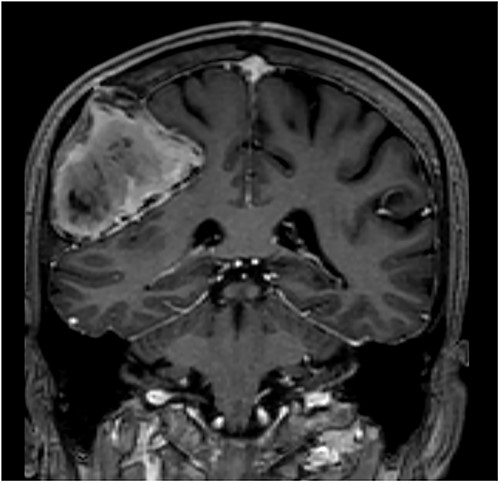

T1-weighted contrast-enhanced coronal MRI scan showing the lesion with intralesional haemorrhagic products. There is no evidence of dural invasion.

Our patient is a 76-year-old gentleman with medical history of hypertension and lumbar spondylosis. He did not have any previous history of trauma or systemic infections. He had presented to his local hospital with a 2-day history of left arm numbness. He did not report any headaches or giddiness. On clinical assessment, he did not have any neurological deficits. A CT brain and MRI brain (Figs 1–5) with contrast revealed a 53 × 53 × 41 mm partially calcified, heterogeneously enhancing conical shaped right extra-axial parietal convexity lesion. The overlying calvarial bone was remodelled and possibly eroded. There was evidence of prior haemorrhage within the lesion and scattered internal and peripheral calcification. Based on these characteristics, the possible diagnoses were that of an intraosseous meningioma, haemangioma and giant cell tumour. Patient was consented for craniotomy and excision of the tumour.